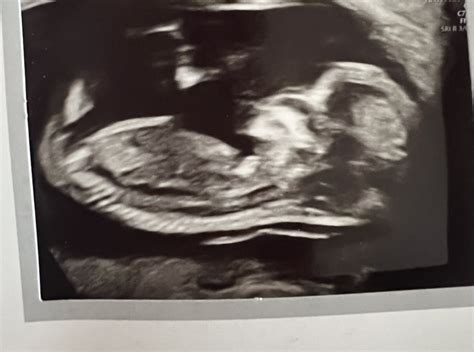

The 20-week scan , also known as the anatomy scan, is a crucial milestone during pregnancy. It’s a detailed ultrasound examination typically performed between 18 and 22 weeks to assess the baby’s physical development and identify any potential abnormalities. Understandably, it’s a nerve-wracking time for expectant parents. Discussions on platforms like Mumsnet reveal that many women experience anxiety leading up to this scan, and a significant concern revolves around the possibility of receiving unexpected or unfavorable news. So, how common is it to receive bad news at the 20-week scan? What kind of issues might be detected, and how are these situations typically handled? Let’s dive into these questions, drawing insights from real experiences shared on Mumsnet, to provide a comprehensive overview for those navigating this important stage of pregnancy.